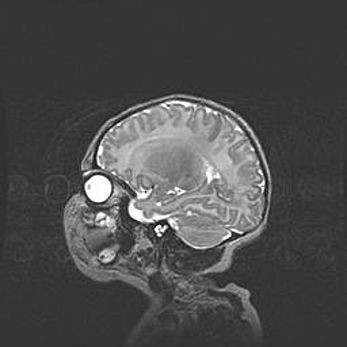

Лейкомаляция с кистозно-глиозной дегенерацией головного мозга.

Возраст: 2 месяца 25 дней

Вес: 6400 г

Окружность головы: 40 см

Срок гестации: 41 неделя

Лейкомаляцию относят к ишемически-гипоксическим повреждениям головного мозга, диагностируемым у новорожденных. При лейкомаляции в головном мозге обнаруживают очаги некроза, возникшие после тяжелой гипоксии и нарушения кровотока. В процессе морфогенеза очаги проходят три стадии: 1) развития некроза, 2) резорбции и 3) формирования глиозного рубца или кисты. Перивентрикулярная лейкомаляция (ПЛ) встречается примерно в 12% случаев среди новорожденных, обычно – у недоношенных детей, причем, частота ее зависит от массы, с которой младенец появился на свет. Наибольшее число малышей страдает лейкомаляцией, если масса при рождении 1500-2500 г.